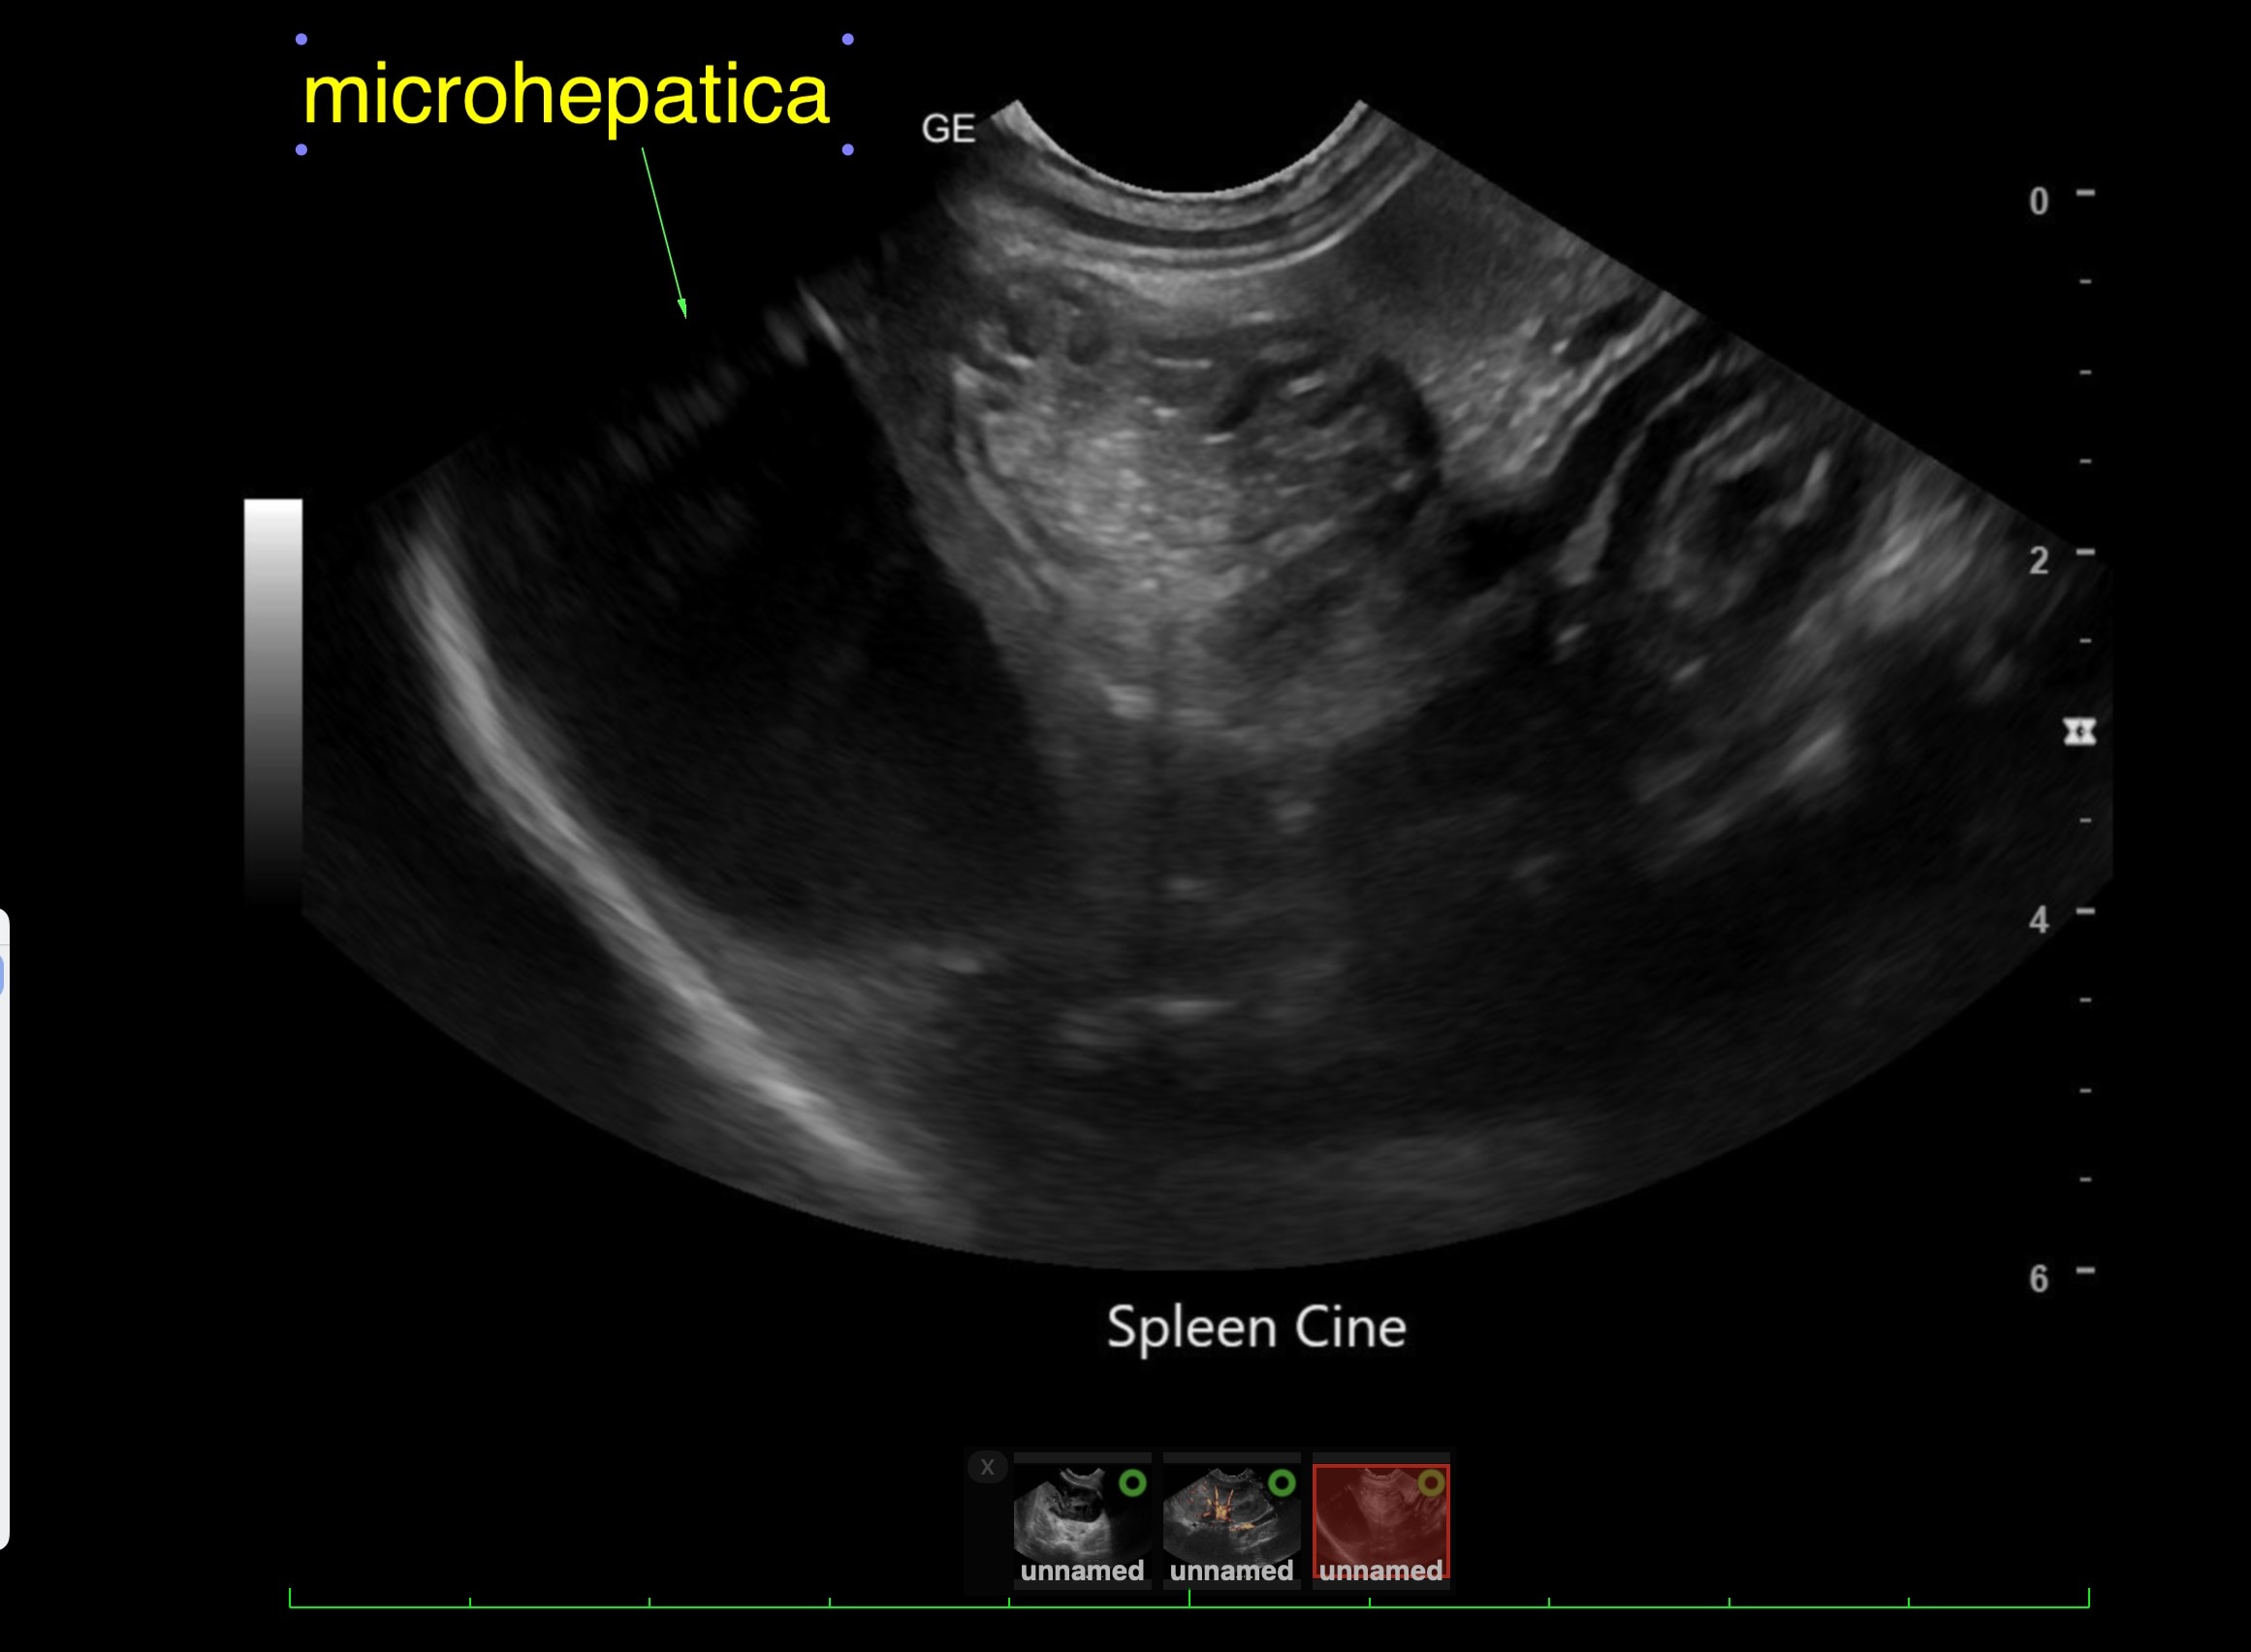

PE: BCS 3/9, unkempt/fuzzy haircoat, peripheral blindness, pacing room and clinging to wall.

Labwork (fasted): TP 4.5, Alb 2.5, ALP 144, ALT 155, GGT 3, Bili 0.4, Cre 0.3, Cho 51, Amy 266 CBC – HCT 39%, Hgb 12.0 UA – USG 1.030pH 6, 1+ bilirubin, WBC 4-10/hpf, rods 26-50/hpf Negative Accuplex Bile Acids: Pre 299.2, Post-meal – 90.7